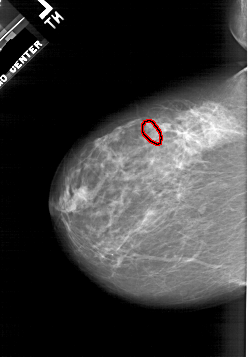

A_1941_1.LEFT_CC

LEFT_CC LINES 5701 PIXELS_PER_LINE 3976 BITS_PER_PIXEL 12 RESOLUTION 43.5 OVERLAY

FILE: A_1941_1.LEFT_CC.OVERLAY

TOTAL_ABNORMALITIES 1

ABNORMALITY 1

LESION_TYPE CALCIFICATION TYPE PLEOMORPHIC DISTRIBUTION CLUSTERED

ASSESSMENT 4

SUBTLETY 2

PATHOLOGY BENIGN

TOTAL_OUTLINES 1

BOUNDARY